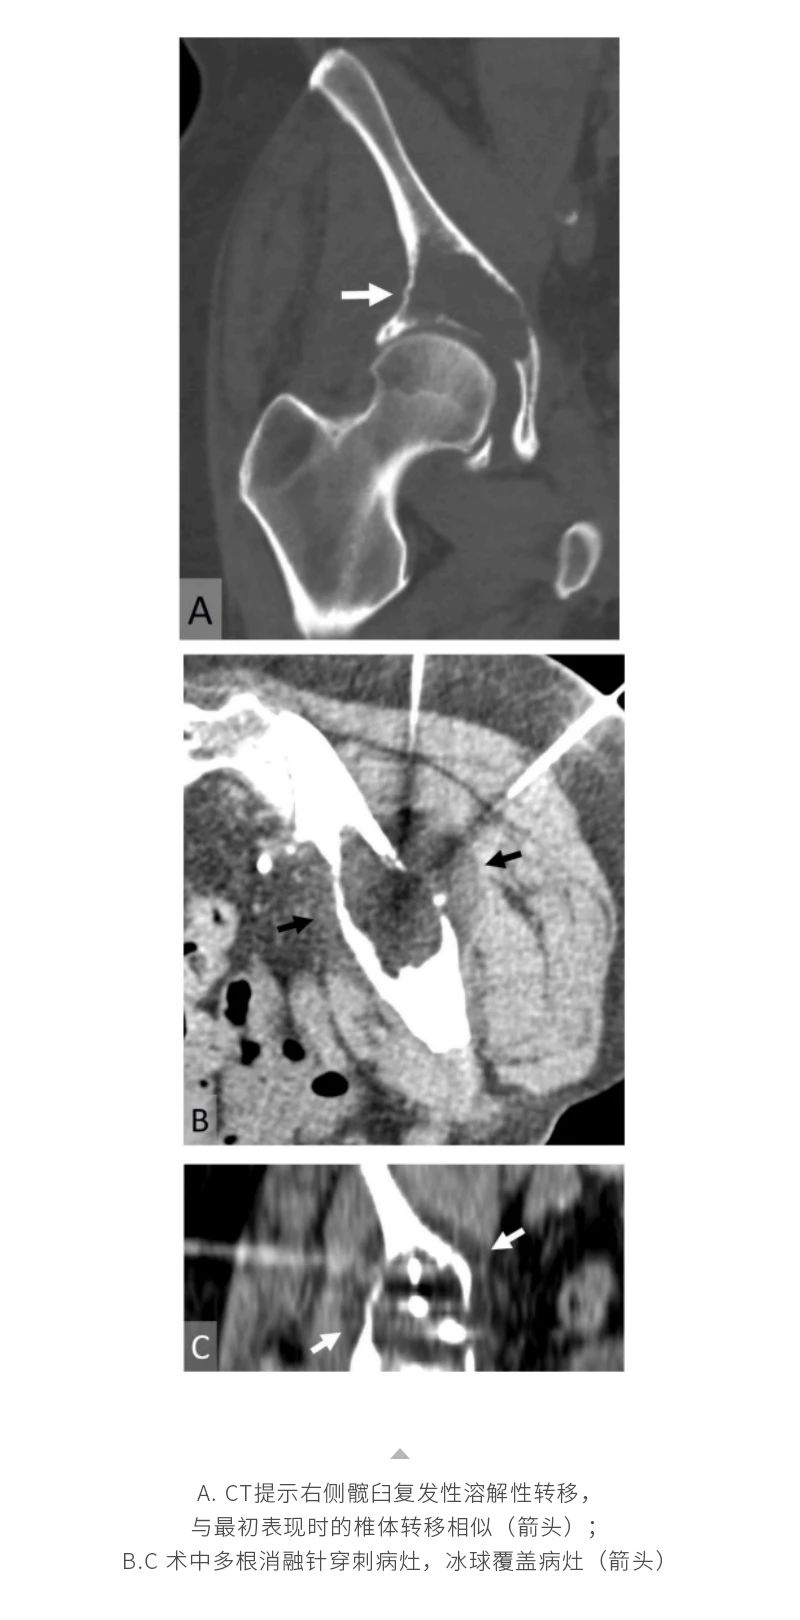

冷凍消融骨腫瘤——【海杰亞科研資訊】第285期

發(fā)布時(shí)間:2024-10-18 | 作者:海杰亞 | 瀏覽次數(shù):1127